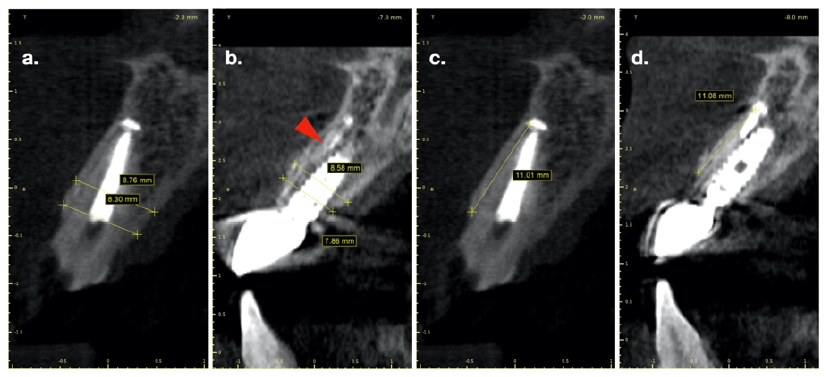

The Use of a 0.8 mm Drill Associated with an Endodontic Guide to Access a Flatted Calcified Canal: A Case Report

Taia Maria Berto Rezende, Marcelo Moreti, Paula Guimarães Dominguete, Poliana Amanda Silva and Sonia Teresa de Oliveira Lara-Mendes. 22(5): 70-74.